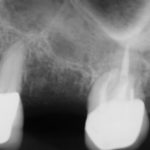

Anthony A.

This patient had only a few remaining infected teeth, but didn’t want to settle for just a denture.  Placed multiple implants and provided a secure fixed option which allowed him to not only chew better but to smile again.